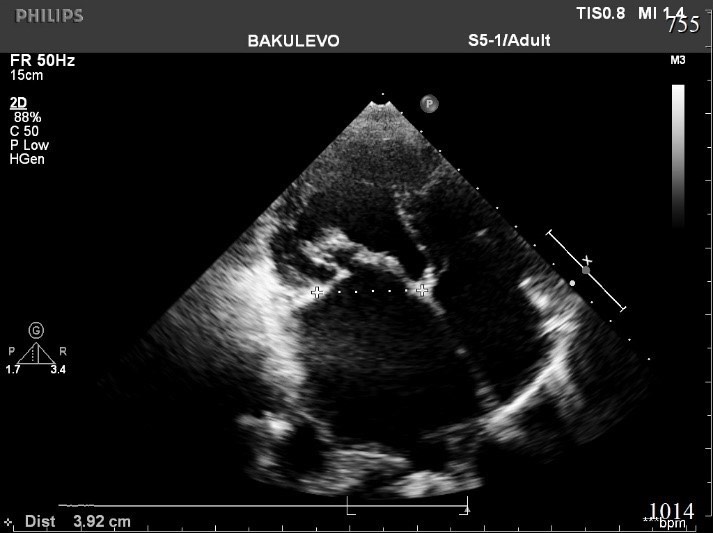

1918. На эхокардиографическом изображении представлен